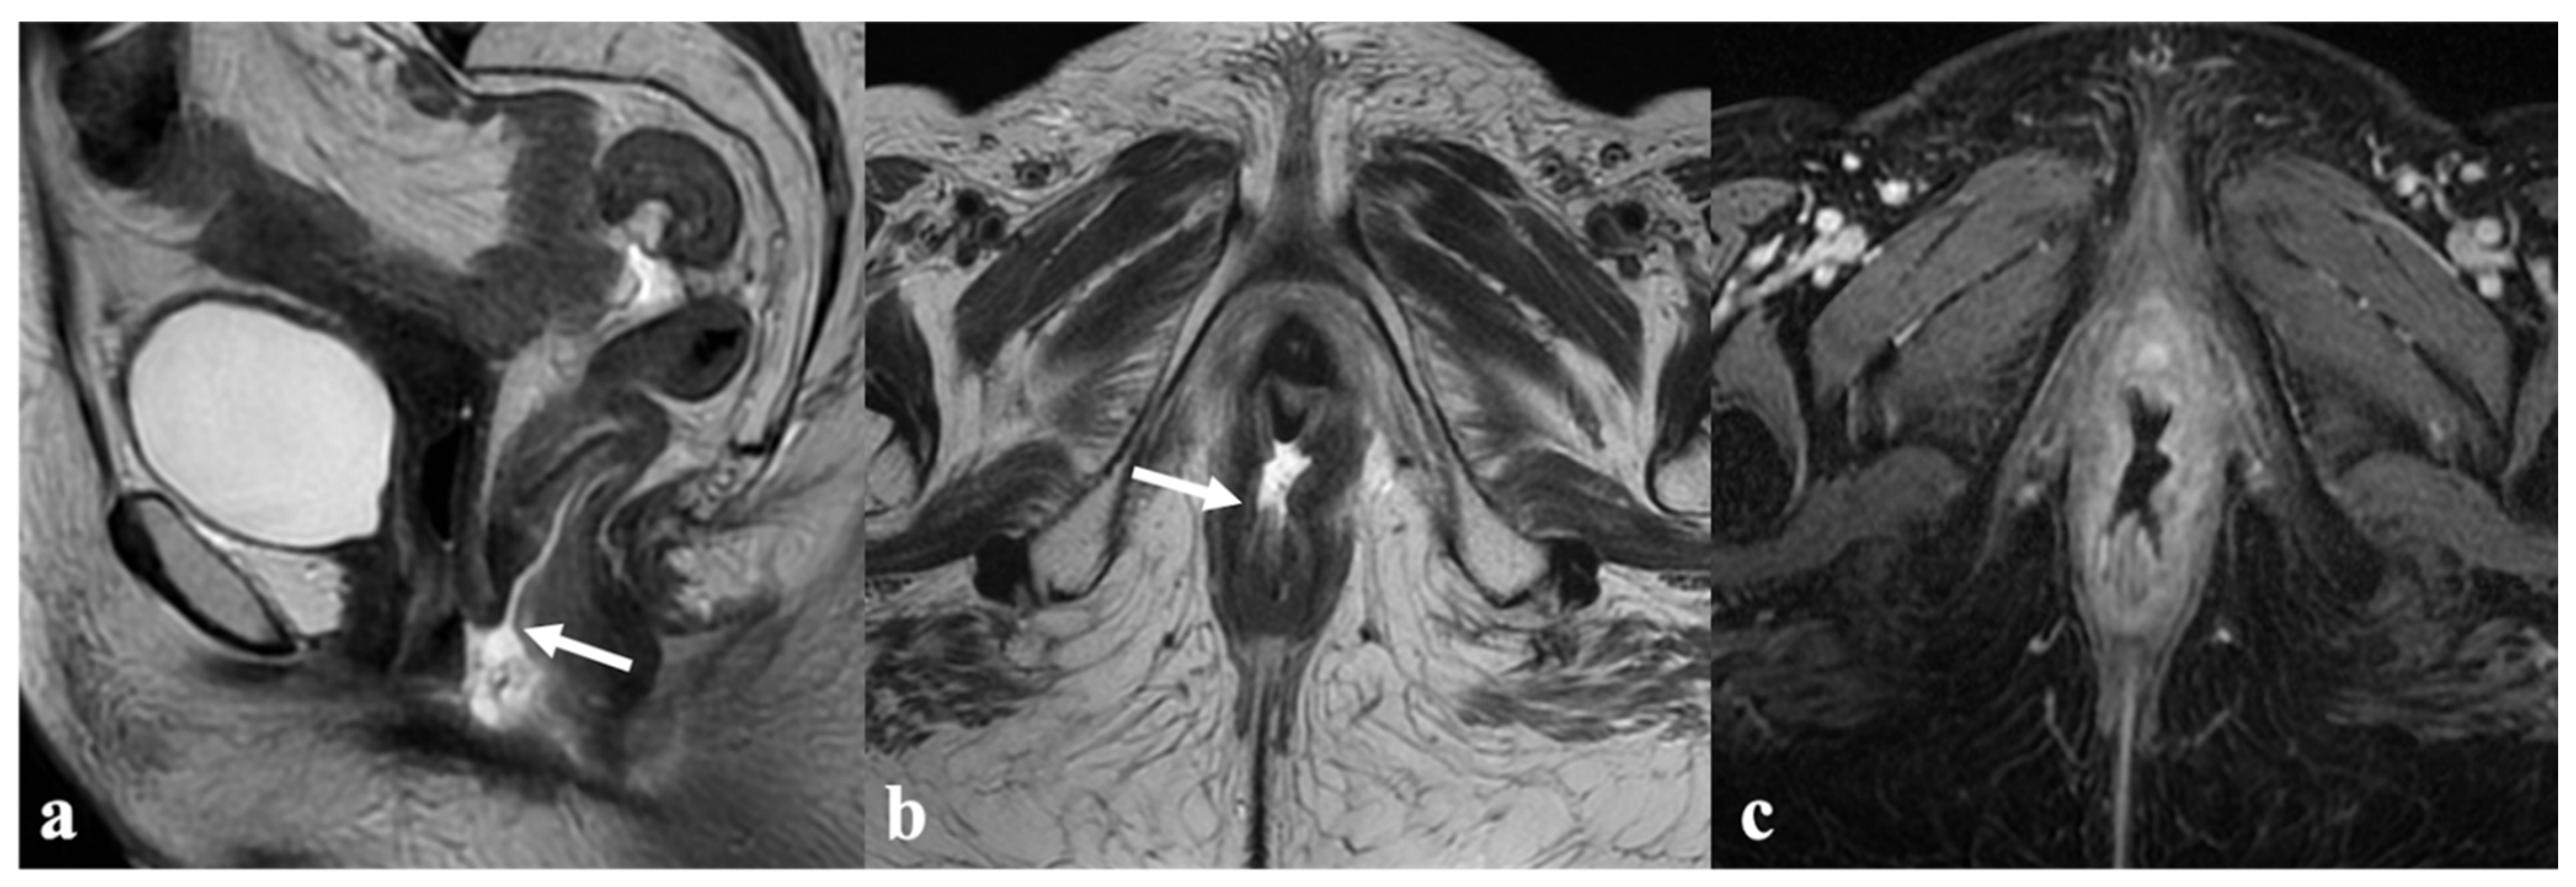

5. Vulvar Cancer Recurrence

6. Post-Therapy Complications